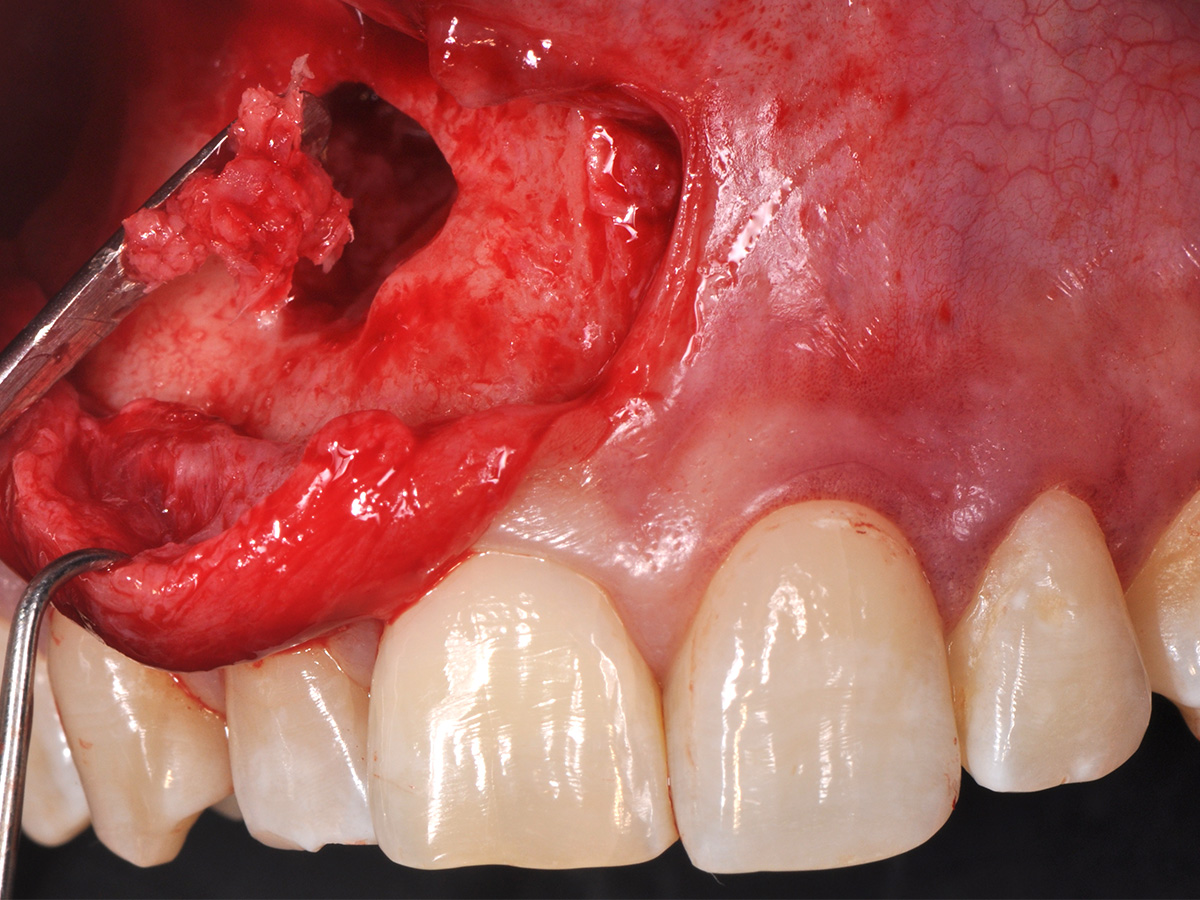

Abbildung 8

Die Schnittführung wurde aufgrund des bestehenden „Gummy Smile“ hoch im Vestibulum geführt...

Abbildung 9

...so konnte die delikate Parodontalstruktur in ihrer Form unangetastet belassen werden, um einen möglichst optimalen ästhetischen Erfolg zu erreichen.

Mit der Patientin wurde der Versuch des Zahnerhaltes trotz ausgedehnter Zyste besprochen. Gleichzeitig sollte das Zystenlumen zu einer sicheren ossären Durchbauung geführt werden, um eine implantologische Sofortversorgung vorzubereiten, falls zu einem späteren Zeitpunkt eine Zahnentfernung notwendig werden sollte. In der Phase vor der geplanten Operation wurden die Wurzelkanalfüllungen an Zahn 11 und 12 durch einen Endodontologen alio loco revidiert. Die Schnittführung wurde aufgrund des bestehenden „Gummy Smile“ hoch im Vestibulum geführt – so konnte die delikate Parodontalstruktur in ihrer Form unangetastet belassen werden, um einen möglichst optimalen ästhetischen Erfolg zu erreichen (Abb. 8, 9). Nach vestibulärer Freilegung wurde die Zyste vollständig entfernt und zur histopathologischen Untersuchung eingesandt (Abb. 10). Anschließend erfolgte eine Wurzelspitzenresektion an den Zähnen 11 und 12 durch die vestibuläre ossäre Perforation (Abb. 11), gefolgt von einer ultraschallbasierten, retrograden Kanalaufbereitung und Abdichtung mit MTA. Um die knöcherne Durchbauung am Boden der Zyste osteoinduktiv zu unterstützen, wurden mit Hilfe eines mechanischen Knochenschabers aus dem Bereich des rechten naso-palatinalen Pfeilers Knochenchips entnommen und als erste basale Augmentationsschicht in den ossären Defekt eingebracht (Abb. 12). Der größere Anteil von 80 % des Defektvolumens wurde mit einem vollständig resorbierbaren, xenogenen Augmentationsmaterial aufgefüllt (Abb. 13) (mp3®, OsteoBiol®). Der Defekt wurde zum Vestibulum hin mit einer stabilen, vollständig degradierbaren Membran abgedeckt (Abb. 14) (Soft Cortical Lamina, OsteoBiol®). Zum einen wurde hiermit im Sinne der GBR das Weichgewebe vom Augmentat getrennt. Zum anderen verhinderte die stabile Membran das Einwachsen eines Weichgewebeankers in den Defekt und damit eine narbige Verziehung im Vestibulum. Um eine Verschiebung der Membran zu vermeiden, wurde diese mit zwei Titanpins in der Kortikalis fixiert. Die Pins wurden bei Beschwerdefreiheit in situ belassen (Titan-Bone-Pin-System). Der Wundverschluss erfolgte einschichtig mit nicht resorbierbarem Nahtmaterial (Abb. 15) (Seralene® 5-0 DS-15). Peri- und postoperativ wurde eine antibiotische Abschirmung unter Fortführung für insgesamt drei Tage mit Amoxiclav 875/125 1-0-1 durchgeführt.